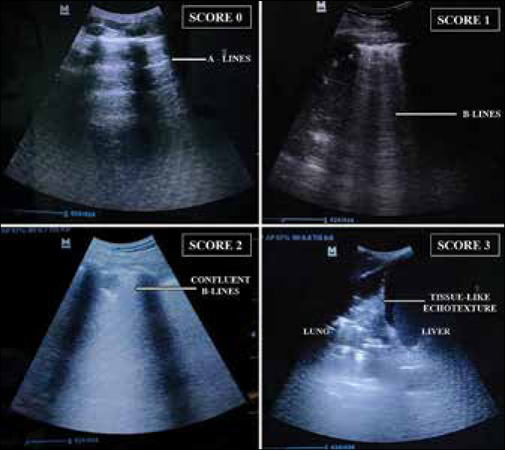

Background: Lung ultrasound (LUS) is a known imaging modality employed for monitoring patients in an intensive care unit. This study evaluates, LUS in assessing disease severity and prognosis, by correlating its score with the three commonly used clinical severity scoring systems (CSSS), namely, sequential organ failure assessment (SOFA) score, acute physiology and chronic health evaluation (APACHE) II score, and simplified acute physiology score (SAPS) II.

Methods: This single-center prospective observational study included 54 adult patients of primary lung disease-induced acute respiratory distress syndrome (ARDS), on invasive ventilation. The primary objective was to correlate LUS score with SOFA score. Secondary objectives were to correlate LUS score with APACHE II and SAPS II scores. LUS score was also correlated with the estimated mortality derived from the above-mentioned scores. A subgroup analysis on COVID-19-positive cases was also carried out. All scores were calculated on the initiation of mechanical ventilation, daily for 7 days or mortality, whichever was earlier.